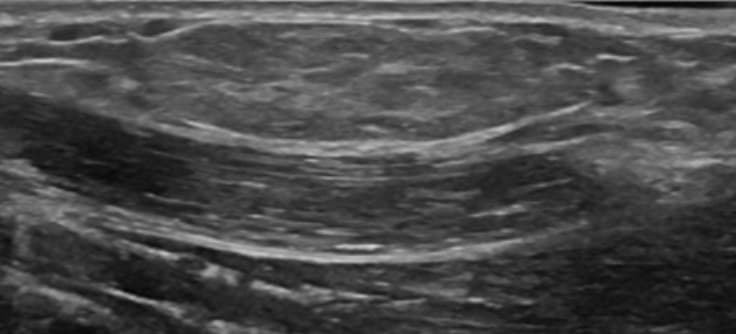

주로 어깨나 팔에 발생하지만, 다른 부위에서도 발생하며, 다발성일 수 있다. 연조직 지방종(soft tissue lipoma)은 피부밑 지방층, 근육 내, 또는 조직사이의 경계면에서 발견된다. 피부밑 연조직의 지방종은 둥그스름하고, 균질한 낮은 또는 같은 에코를 가지며, 색도플러에서 혈류가 없고, 탐촉자로 누르면 모양이 쉽게 변화하는 부드러운 종양이다. 지방종의 에코가 다양한 것은 종괴 안의 지방 및 결합조직의 양, 주변조직의 에코에 따라 달라지기 때문이다. 예를 들면, 균질한 지방종은 낮은 에코로 보인다. 종괴 안의 섬유질이 많으면 종괴는 더 낮은 에코를 보이게 된다. 지방종이 근육 안에 있게 되면, 초음파소견은 비특이적이지만, 종종 경계가 불분명한 높은 에코의 종괴로 보인다. 에코가 비슷한 피하지방층에 지방종이 있으면 초음파 검사에서 곧바로 구별이 안 될 때가 있다. 이때는 이학적 검사에서 만져지는 종괴를 손으로 만진 상태에서 검사를 한다. 종괴가 크거나 통증을 동반하는 경우에는 MRI 검사나 병리조직 검사가 필요하다.

지방종 초음파 영상 피부밑 지방층에서 높은에코의 작은 종괴가 있을 때는 추가적으로 혈관지방종(angiolipoma)이나 과오종(hamartoma)등을 감별진단에 포함한다. 과오종은 환자의 50%에서 통증을 동반하는 다발성 종괴로 나타난다. 지방층염(panniculitis)또는 외상 후에 생기는 피부밑 지방괴사(fat necrosis)는 다양한 에코를 가질 수 있지만 매우 비슷해 보인다.